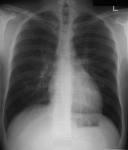

3. Remain still during the exposure, which lasts only a few seconds. Motion makes the images blurry and requires them to be repeated, adding to radiation exposure. For certain exams, you will be asked to hold your breath so your moving lungs will not blur the image. The easiest way to do this is to take a deep breath, exhale and then take another deep breath and hold it.